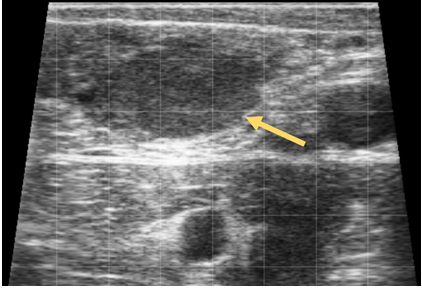

What is the yellow arrow pointing to?

Corpus luteum from ultrasound (cow)